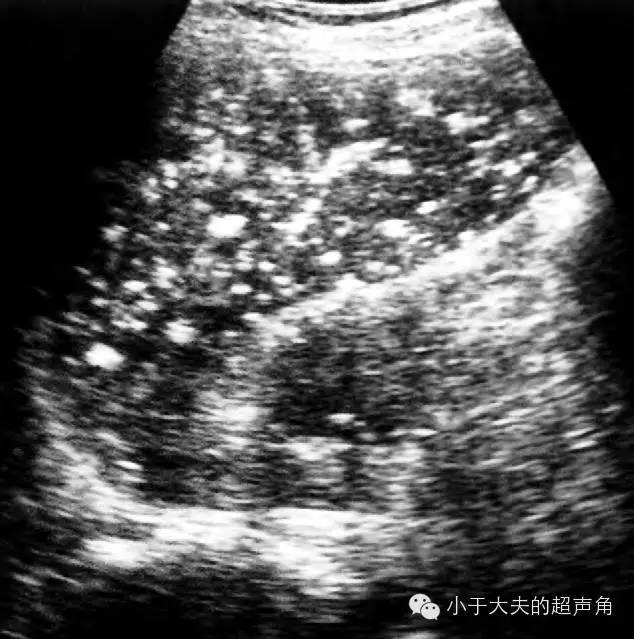

【超声随响】第14期 脾结核 splenic tuberculosis